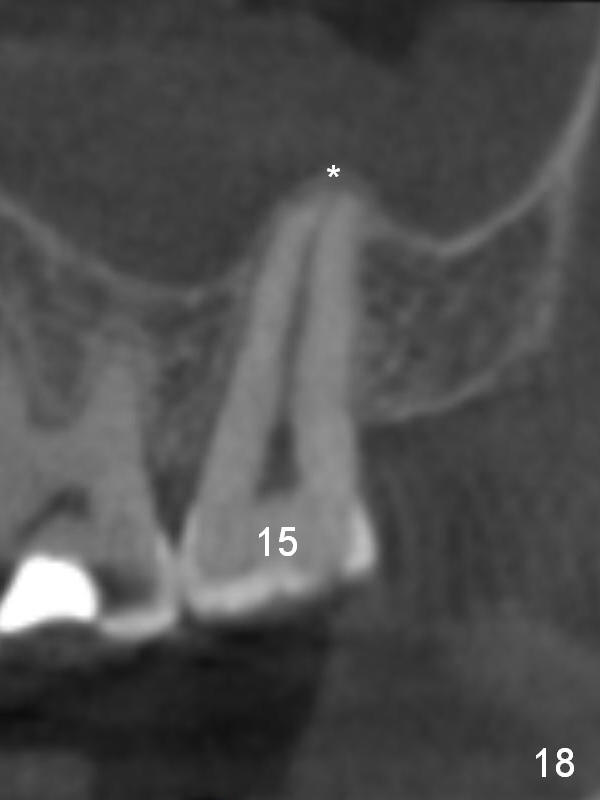

CBCT taken 23 months post cementation shows no abnormality (Fig.15-17). On the contralateral side, the apex of the tooth #15 is immediately inferior to the sinus floor (Fig.18 (sagittal section), 19 (coronal section)). The immediate implant seems to be unavoidably entering the sinus. The implant seems to be normal 3 year 5 months post cementation.